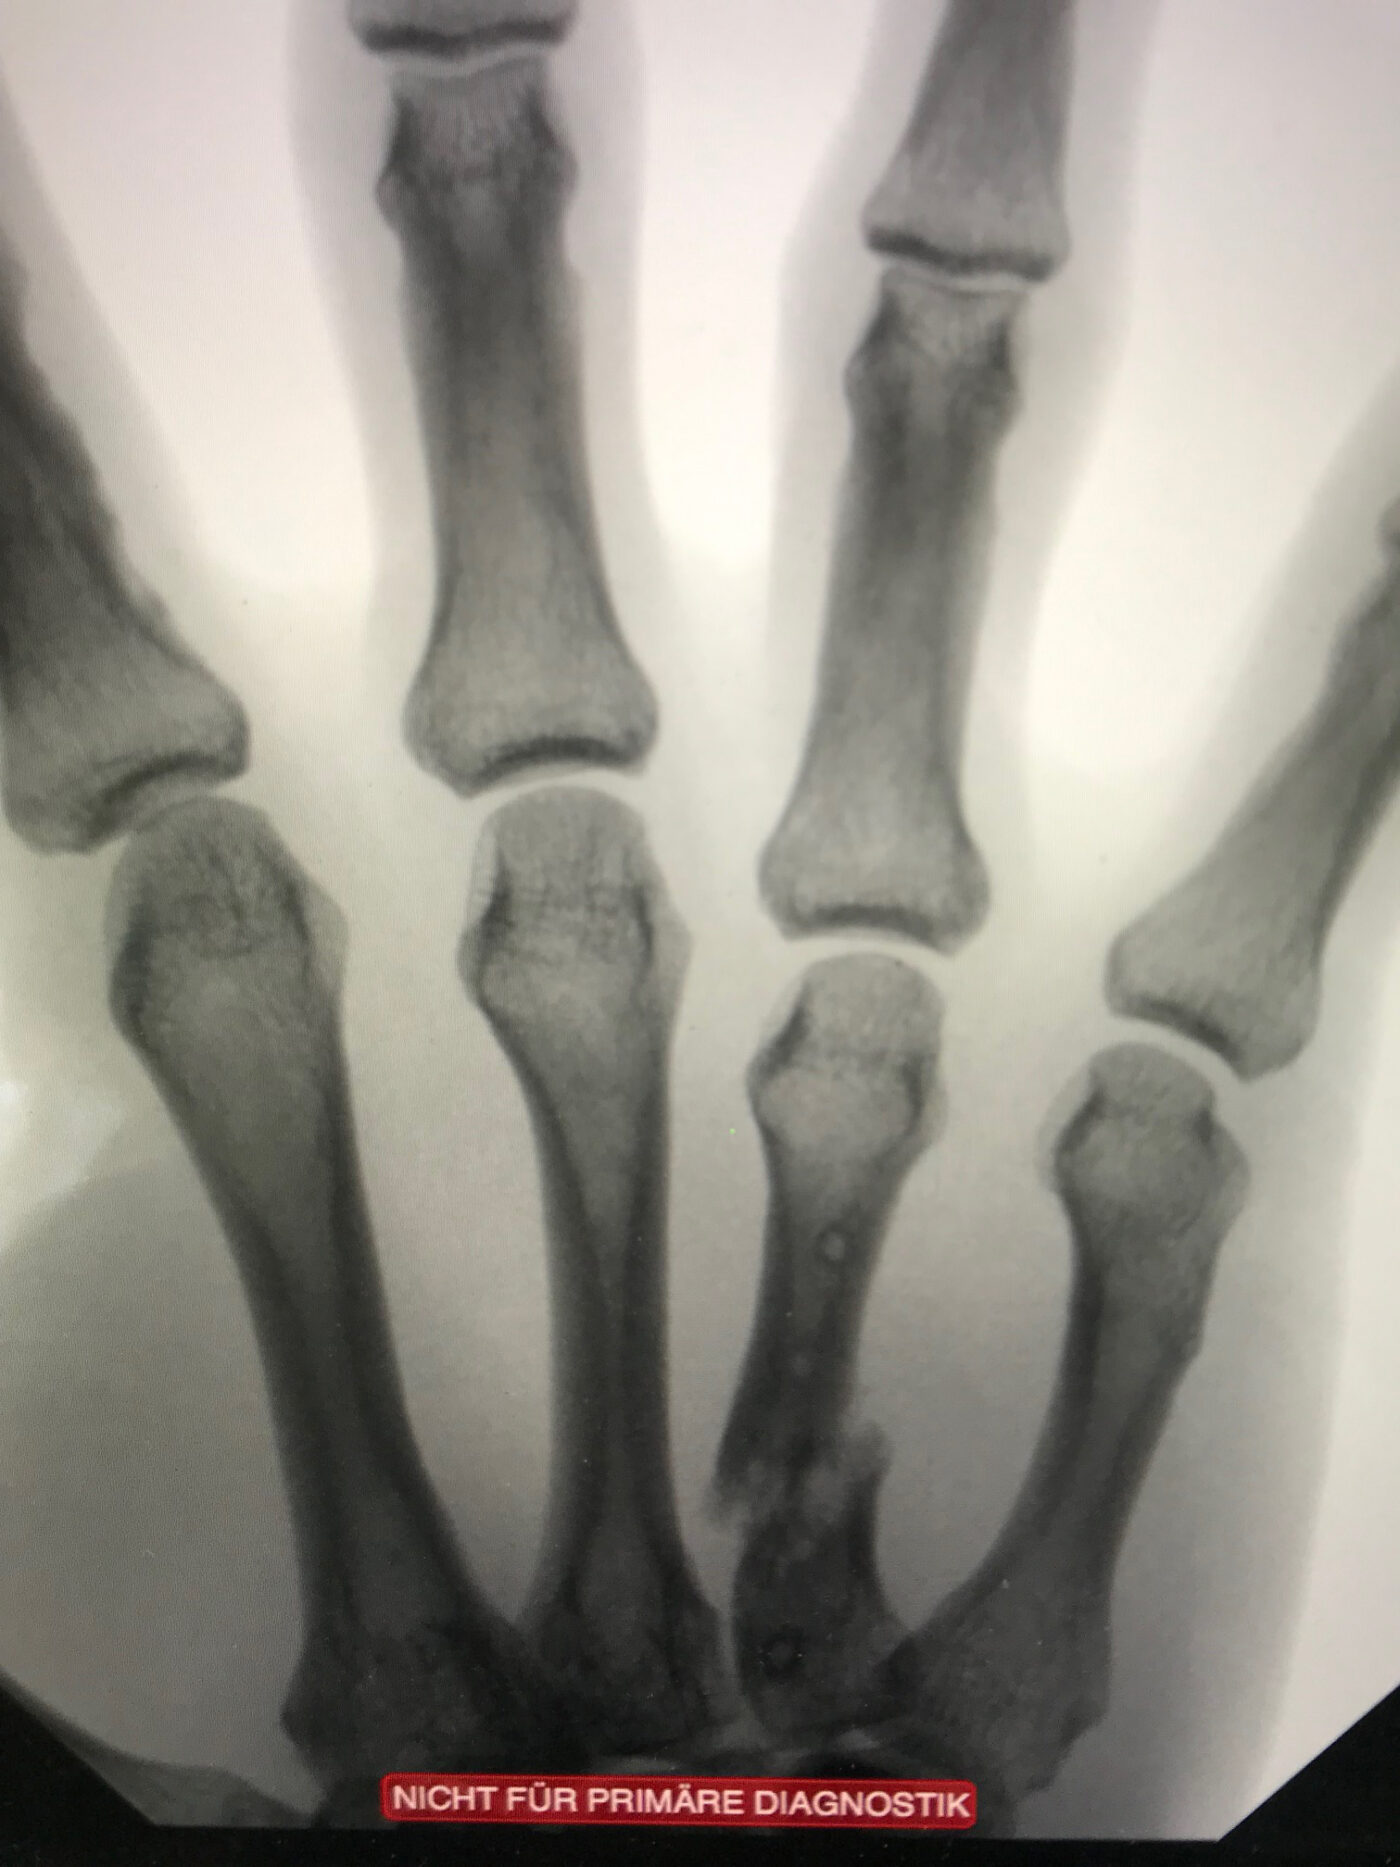

Il en résulte, pour le Canadien, une quatrième fracture à la main droite: après une fracture de l’index et une fracture complexe du pouce, un autre doigt se brise sous l’extrême violence du palet. «Du point de vue médical, il aurait fallu opérer immédiatement. L’attente a impliqué un doigt de plus en plus tordu et raccourci», explique le Dr Kay Jürgensen.

Mais ce genre de considérations et de douleurs ne retiennent pas un hockeyeur loin de la glace: un strap autour du poignet fait l’affaire. Le chirurgien laisse donc le joueur partir avec un: «As long as you win». Une semaine après la victoire du CPB et le temps de laisser les joueurs la fêter, l’intervention a enfin lieu. C’est une opération de reconstruction complexe, lors de laquelle le Dr Kay Jürgensen transplante de l’os prélevé dans le radius dans le métacarpe – pour combler le trou existant. «J’ai remis le doigt dans le bon alignement et lui ai redonné sa longueur».